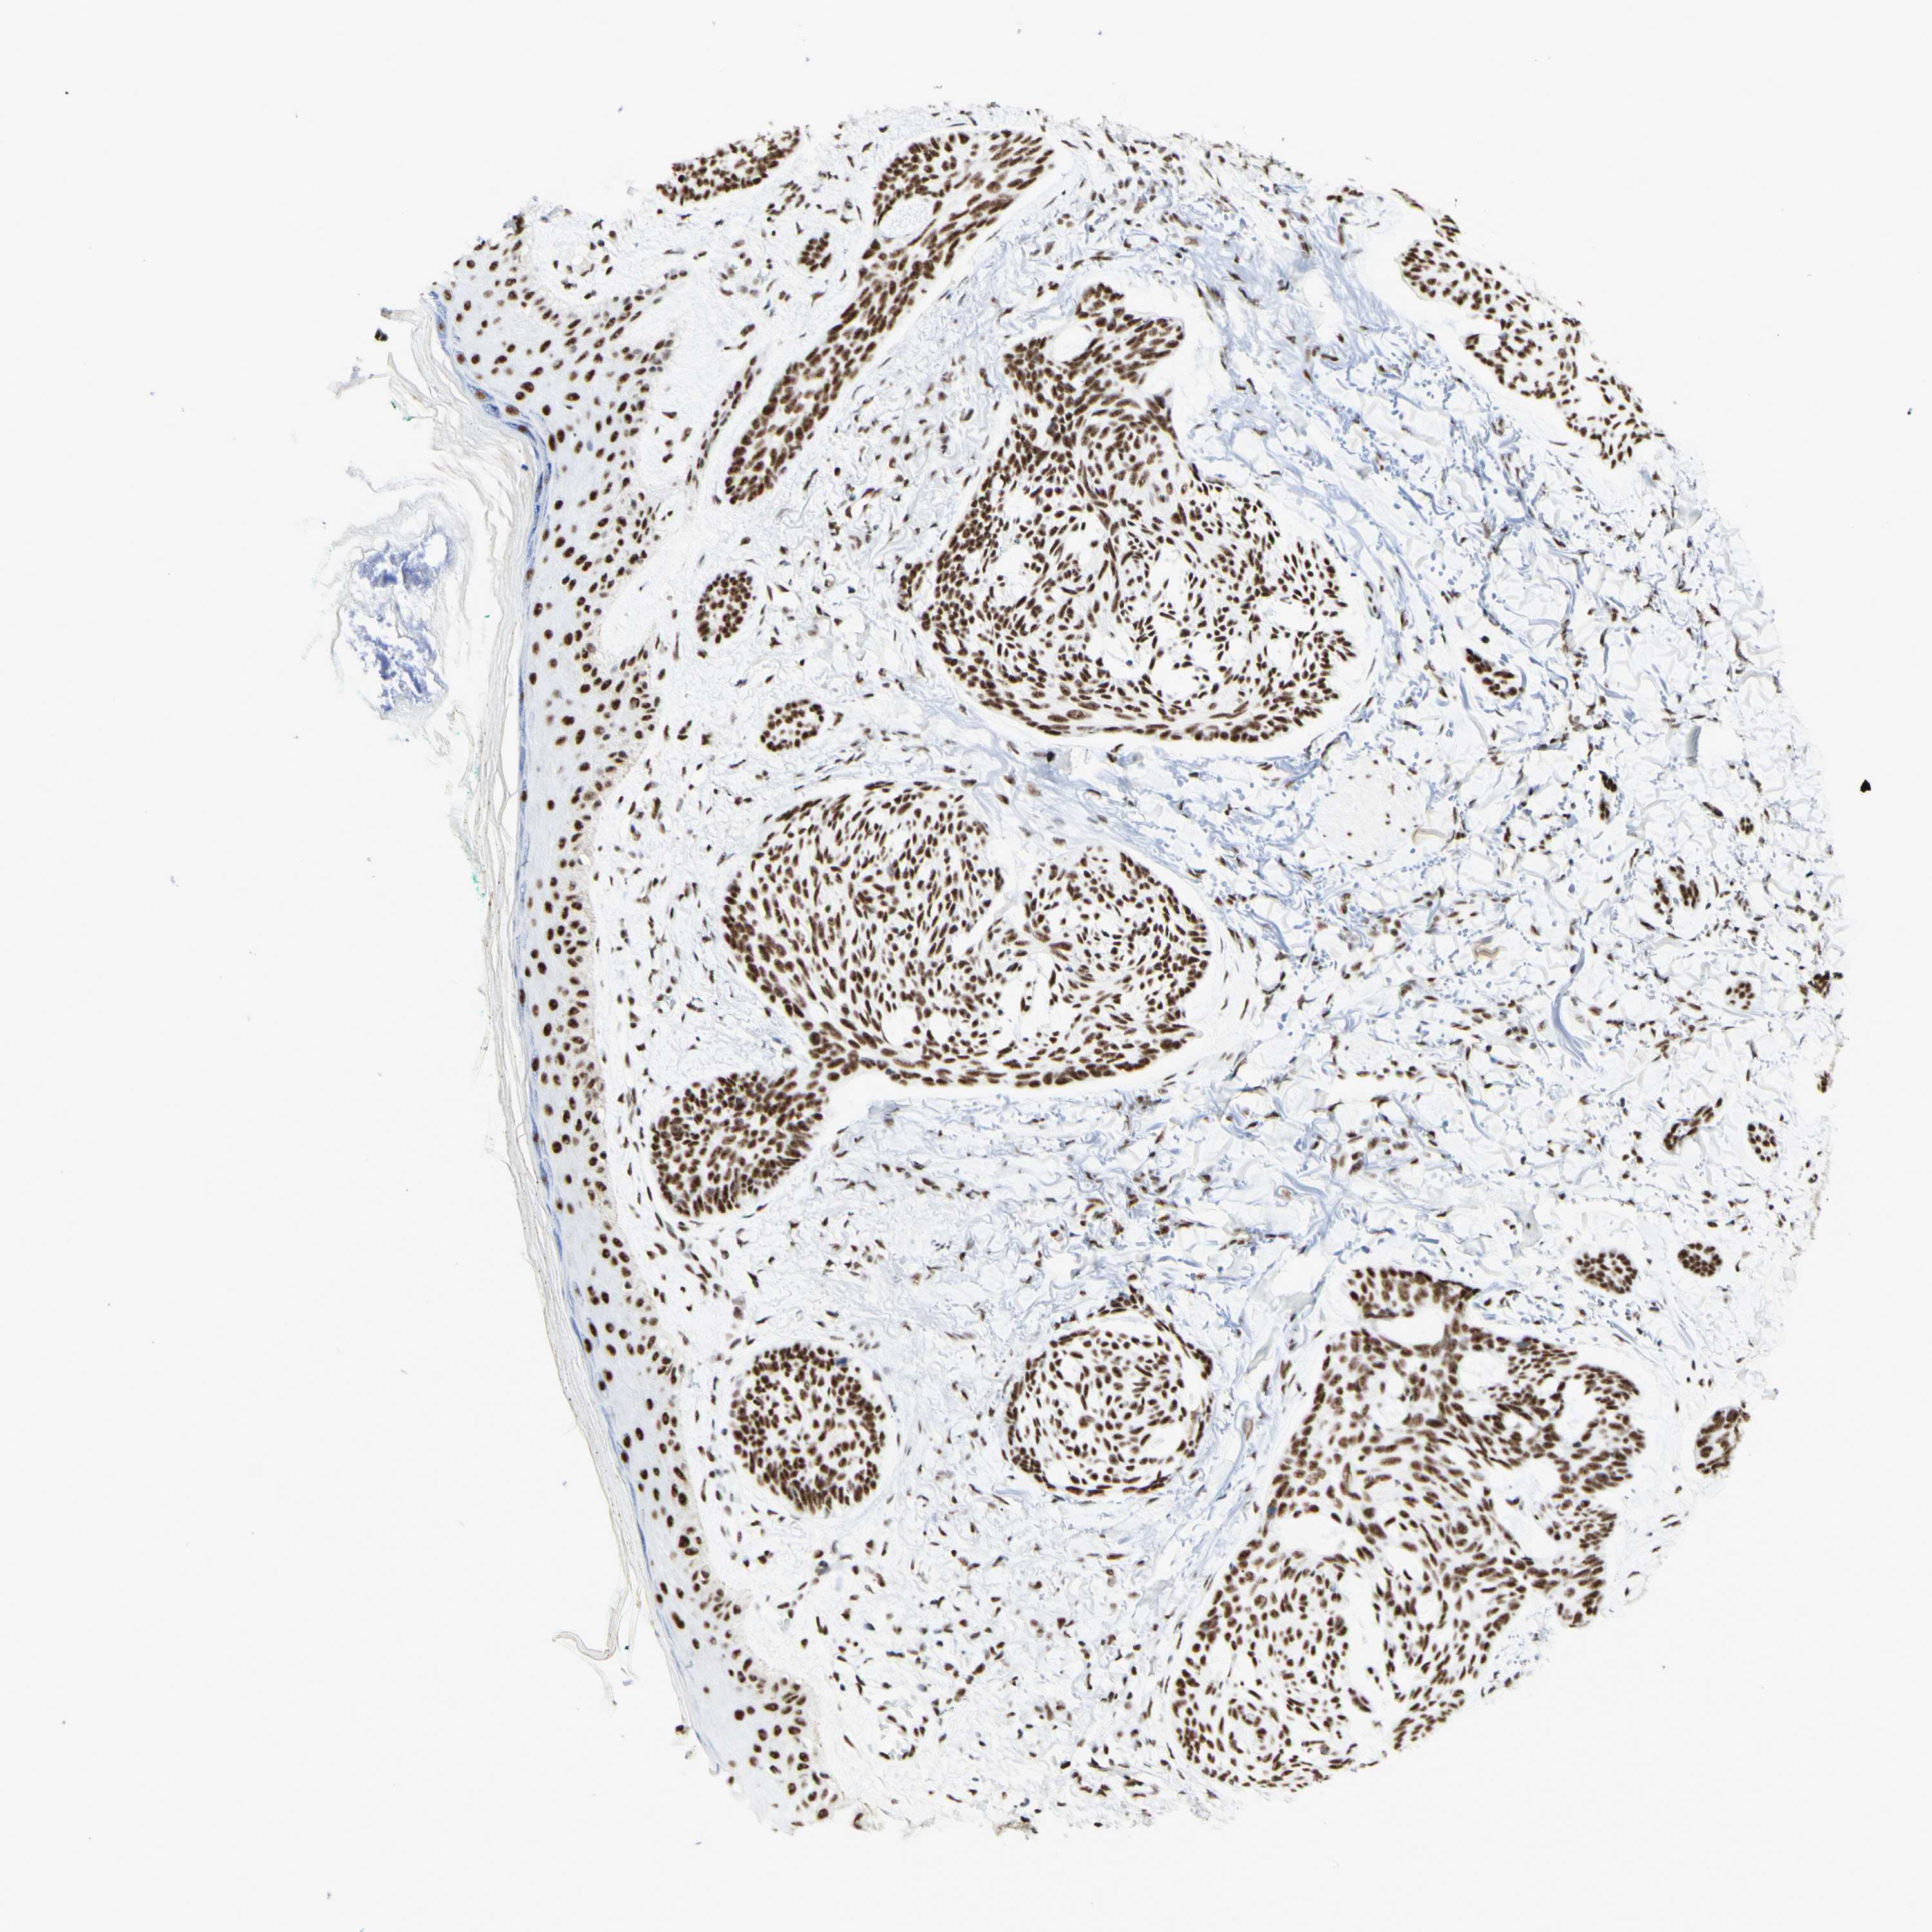

SKIN CANCER - Protein expressioni

A mouse-over function shows sample information and annotation data. Click on an image to view it in a full screen mode. Samples can be filtered based on level of antibody staining by selecting one or several of the following categories: high, medium, low and not detected. The assay and annotation is described here.

Antibody stainingi

Antibody staining in the annotated cell types in the current human tissue is reported as not detected, low, medium, or high, based on conventional immunohistochemistry profiling in selected tissues. This score is based on the combination of the staining intensity and fraction of stained cells.

Each image is clickable and will lead to virtual microscopy that enables deeper exploration of all samples and also displays staining intensity scores, fraction scores and subcellular localization as well as patient and tissue information for each sample.

Antibody HPA010550

Staining

High

Medium

Low

Not detected

Intensity

Strong

Moderate

Weak

Negative

Quantity

>75%

75%-25%

<25%

None

Location

Nuclear

Cytoplasmic/membranous

Cytoplasmic/membranous,nuclear

Squamous cell carcinoma, NOS

Basal cell carcinoma